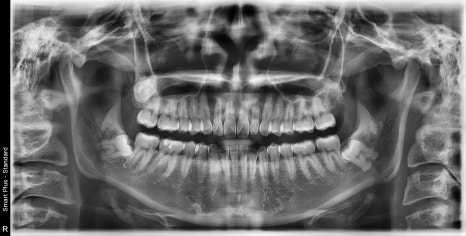

| 발치 전 | 발치 후 |